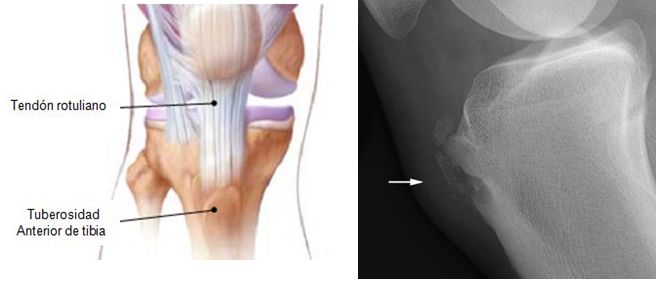

Es una entidad que produce dolor en la región anterior de la rodilla  (tuberosidad tibial), conocida como enfermedad de Osgood-Schlatter (EOS).  La condición, es un resultado de una tracción que ocurre en la tuberosidad tibial a causa del tirón del grupo muscular de los cuádriceps a través del tendón de la rótula.

Actualmente es ampliamente aceptado que la EOS es una tracción del tubérculo tibial debido a esfuerzos repetitivos, y avulsión crónica del centro de osificación secundario de la tuberosidad tibial. El esfuerzo repetitivo es un fuerte tirón del músculo cuádriceps producida durante las actividades deportivas. La avulsión de la tuberosidad tibial puede ocurrir en la fase pre-osificación, o con el centro de osificación secundaria ya osificado.

Una vez que el hueso o cartílago se  separa, sigue creciendo, y osificando  agrandándose. El área intermedia puede llegar a ser fibroso, la creación de una falta de unión localizada (huesecillo persistente separado), o puede mostrar la unión ósea completa con agrandamiento leve de la tuberosidad tibial.

Hallazgos del examen físicode la EOS incluyen sensibilidad a la palpación sobre la tuberosidad de la tibia y, a veces, sensibilidad limitada a la mitad distal del tendón de la rótula. Hinchazón localizada sobre la tuberosidad de la tibia puede estar presente, pero no se ven verdaderos  derrames de rodilla. El paciente puede caminar con una marcha antiálgica, favoreciendo la pierna lesionada, que es  a menudo observado por los padres. El dolor se reproduce con la extensión resistida de rodilla  a partir de 90 grados de flexión de la rodilla.

La elevación de la pierna recta por lo general no es dolorosa, pero si el dolor se asocia con un déficit de extensión (falta de extensión activa de la rodilla completa), hay que diferenciar el dolor agudo severo de EOS, de una fractura por avulsión de la tuberosidad tibial.

Hallazgos de la RM incluyen el engrosamiento y edema del tendón rotuliano distal, la bolsa infrarrotuliana distendida por fluido, el edema del tejido blando circundante, y edema de médula ósea subyacente a la tuberosidad tibial.

Radiografías de la rodilla pueden mostrar la fragmentación del tubérculo tibial, hinchazón de los tejidos blandos, y la obliteración del ángulo inferior de la almohadilla de grasa de Hoffa.